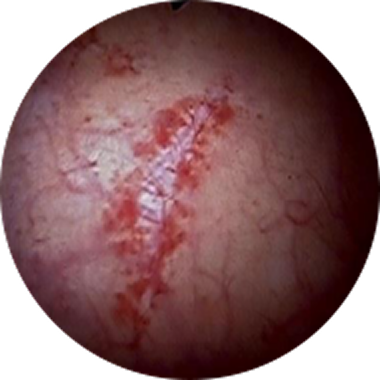

궤양 병변